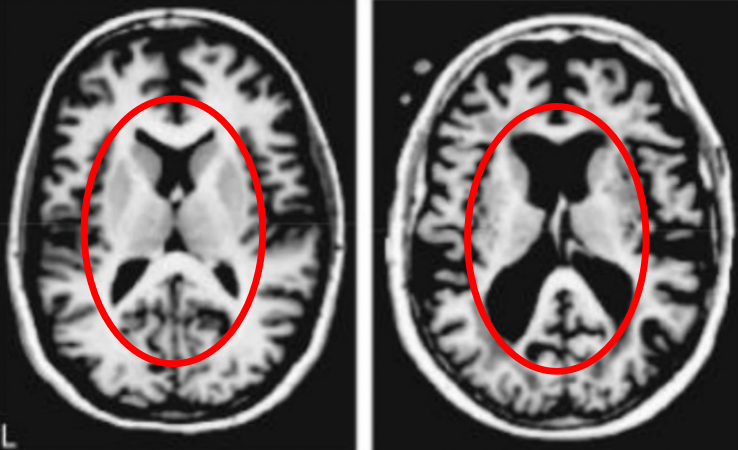

下图中有两张磁共振成像,左侧是年轻人的大脑,右侧是健康老人的大脑。从黑色面积的增加我们能清楚地看到脑组织的萎缩。

人类大脑的结构极为精妙,所以…也极为脆弱,脑萎缩几乎直接意味着多种认知功能受损。所以老年人经常会面对“记不住事”,“眼花耳背”,“手脚不灵便”这些问题。

但需要注意的是,右图中大脑的主人,已经94岁了。对于健康人来说,大脑的衰退…其实是个相当缓慢的过程。

现在我们换另一张图,这张图里的大脑看起来与刚才那张有着相似的萎缩,但它的主人其实是一个只有77岁,但患有阿尔茨海默症的老人。

即使大脑的萎缩和功能衰退不可避免,但阿尔茨海默症会大大加速这个过程。